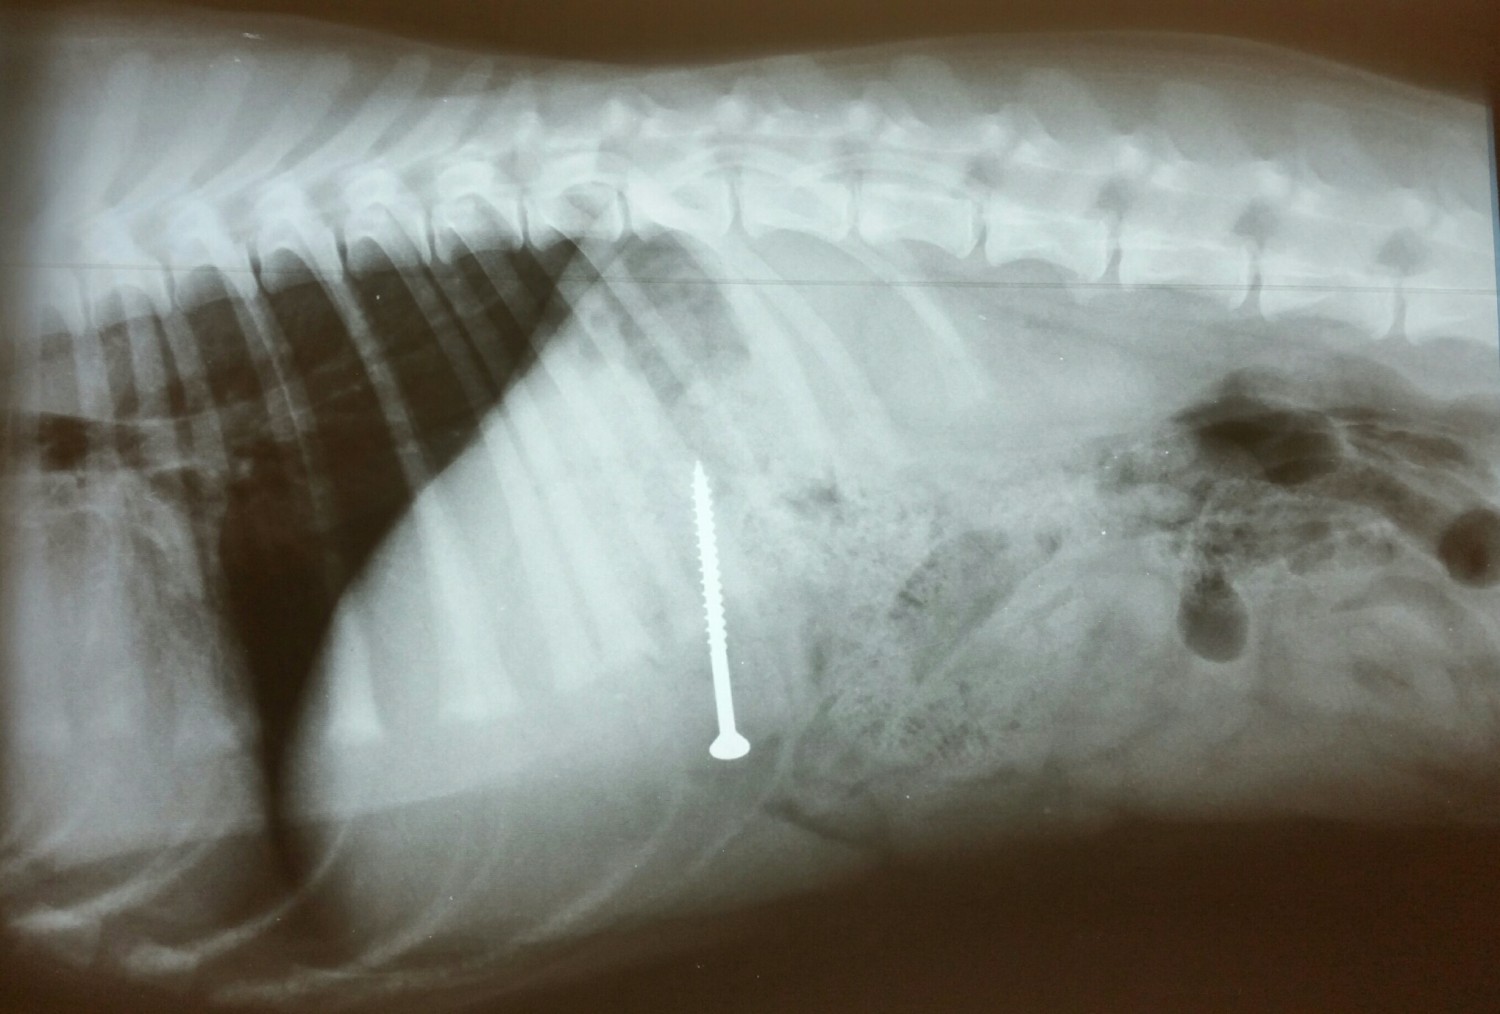

- Рентген. Идеально подходит для поиска металлических предметов, камней и костей. Однако пластик, резину или ткань рентгеновские лучи «не видят». В таких случаях используют контрастное вещество (барий).

Собака съела инородное тело – диагностика: как достоверно узнать о проблеме

Чтобы точно понять, что именно и где находится, визуального осмотра недостаточно. В клинике диагностика «инородки» – это целый комплекс мероприятий. Первым делом врач собирает анамнез, пытаясь узнать у владельца, что именно пропало в доме.